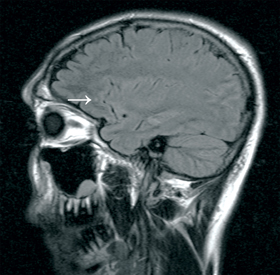

Six patients had abnormalities showing on their MRI scan. Four of these six were male, with a median age of 29 years. The most common MRI abnormality seen (n = 4) was an unidentified bright object (UBO). This is a T2 hyperintensity in subcortical white matter, without a corresponding diffusion-weighted imaging abnormality. Three of the four UBOs seen were in the frontal lobes (Box 3). One patient had cortical atrophy, and one had hippocampal oedema and sclerosis.11 Five of the 23 serious users had abnormalities showing on their MRI scans.

In our pilot study we found that one in five patients had abnormality on their MRI brain scan, the most common being a UBO. Katzman reported only five UBOs as incidental findings in 1000 asymptomatic volunteers (mean age 30.6 years).12 Most UBOs in our study were in the frontal region of the brain; this finding is consistent with reports of frontal abnormalities in MA users.5,13 Whether or not these UBOs are associated with long-term clinical effects is unknown, but our finding supports the possibility of amphetamine use being a risk for cognitive decline, and perhaps an increased risk of stroke.